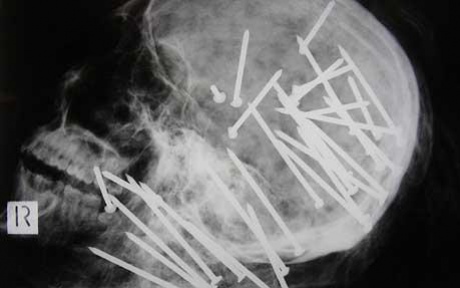

Criminal Activity добавит в Battlefield Hardline четыре новые карты, три вида оружия, две машины, шесть новых масок и неизвестный пока гаджет. Вместе с тем в игре появится едва ли не самый опасный бытовой инструмент — пневматический пистолет, стреляющий гвоздями (подтверждение его опасности — на фото).